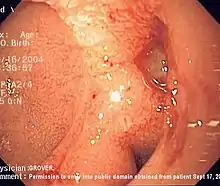

Endoscopic image of adenocarcinoma of duodenum seen in the post-bulbar duodenum.